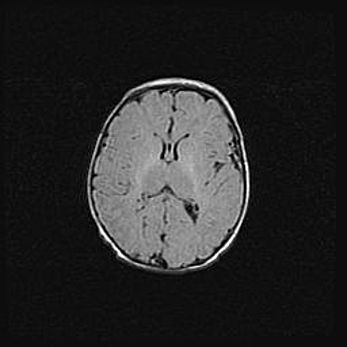

Церебральная ишемия II.

Возраст: 5 дней

Вес: 3400 г

Пол: женский

Окружность головы: 35 см

Срок гестации: 39 недель

Церебральная ишемия – это заболевание, характеризующееся недостаточностью (гипоксией) либо полным прекращением (аноксией) снабжения мозга кислородом по причине закупорки одного или нескольких сосудов. Это приводит к  что метаболическим расстройствам различной степени тяжести в тканях головного мозга, развитию коагуляционных некрозов и гибели нейронов.